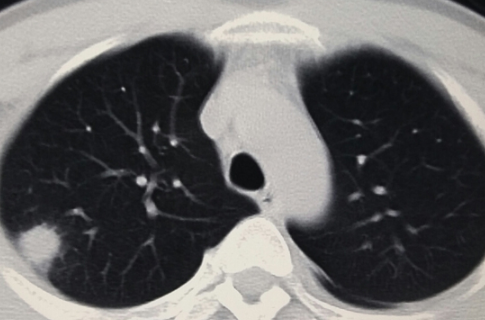

但是X线对软组织的分辨率不是很高,小于一厘米的结节很难发现。现在,越来越多的人在体检时选择胸部CT检查。这样,随着医学影像诊断技术的进步,两到三毫米的肺结节也能被发现和检测到。因此,总的来说,肺结节的发现率越来越高。

正常人群肺结节检出率因地区而异。根据目前的情况,最低可能是20%,最高可能是40%-50%,甚至70%,这可能与参与调查的正常人群有所不同。年龄不一样。 30-70岁的正常人可能会发现70%的人有肺结节,一般在20%-40%左右。肺结节发生率高,但恶性程度低。有可能90%以上的肺结节是良性结节,最终诊断为恶性肿瘤的约有5%左右。